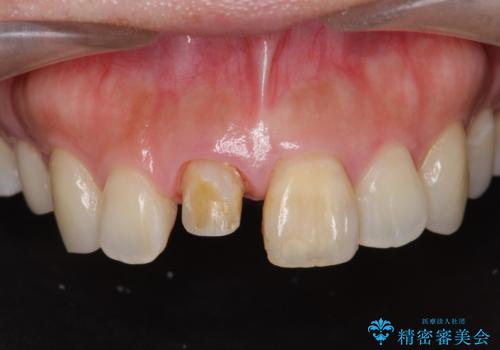

- 歯の神経を除去したのちの、変色の改善を希望され来院されました。

再度根管治療を行ったのちの、オールセラミッククラン治療を計画します。

色調の再現に優れるオールセラミッククラウン スペシャルプランでの治療を希望されました。(保証5年間)